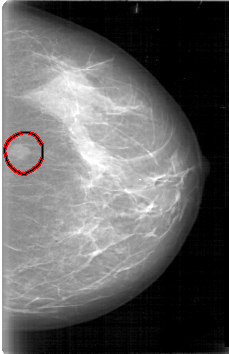

D_4006_1.RIGHT_MLO

FILE: D_4006_1.LEFT_MLO.OVERLAY

TOTAL_ABNORMALITIES 1

ABNORMALITY 1

LESION_TYPE MASS SHAPE OVAL MARGINS OBSCURED

ASSESSMENT 0

SUBTLETY 5

PATHOLOGY BENIGN

TOTAL_OUTLINES 1

BOUNDARY